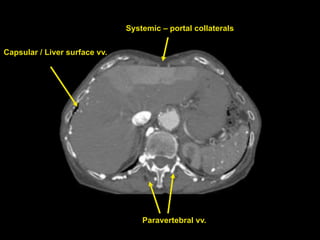

Paravertebral vv. Capsular /Liver surface vv. Systemic – portal collaterals

Venous collaterals organizedby plexus systems – Easier, more complete to report Cihangiroglu: J Comput Assist Tomogr, Volume 25(1).January/February 2001.1-8